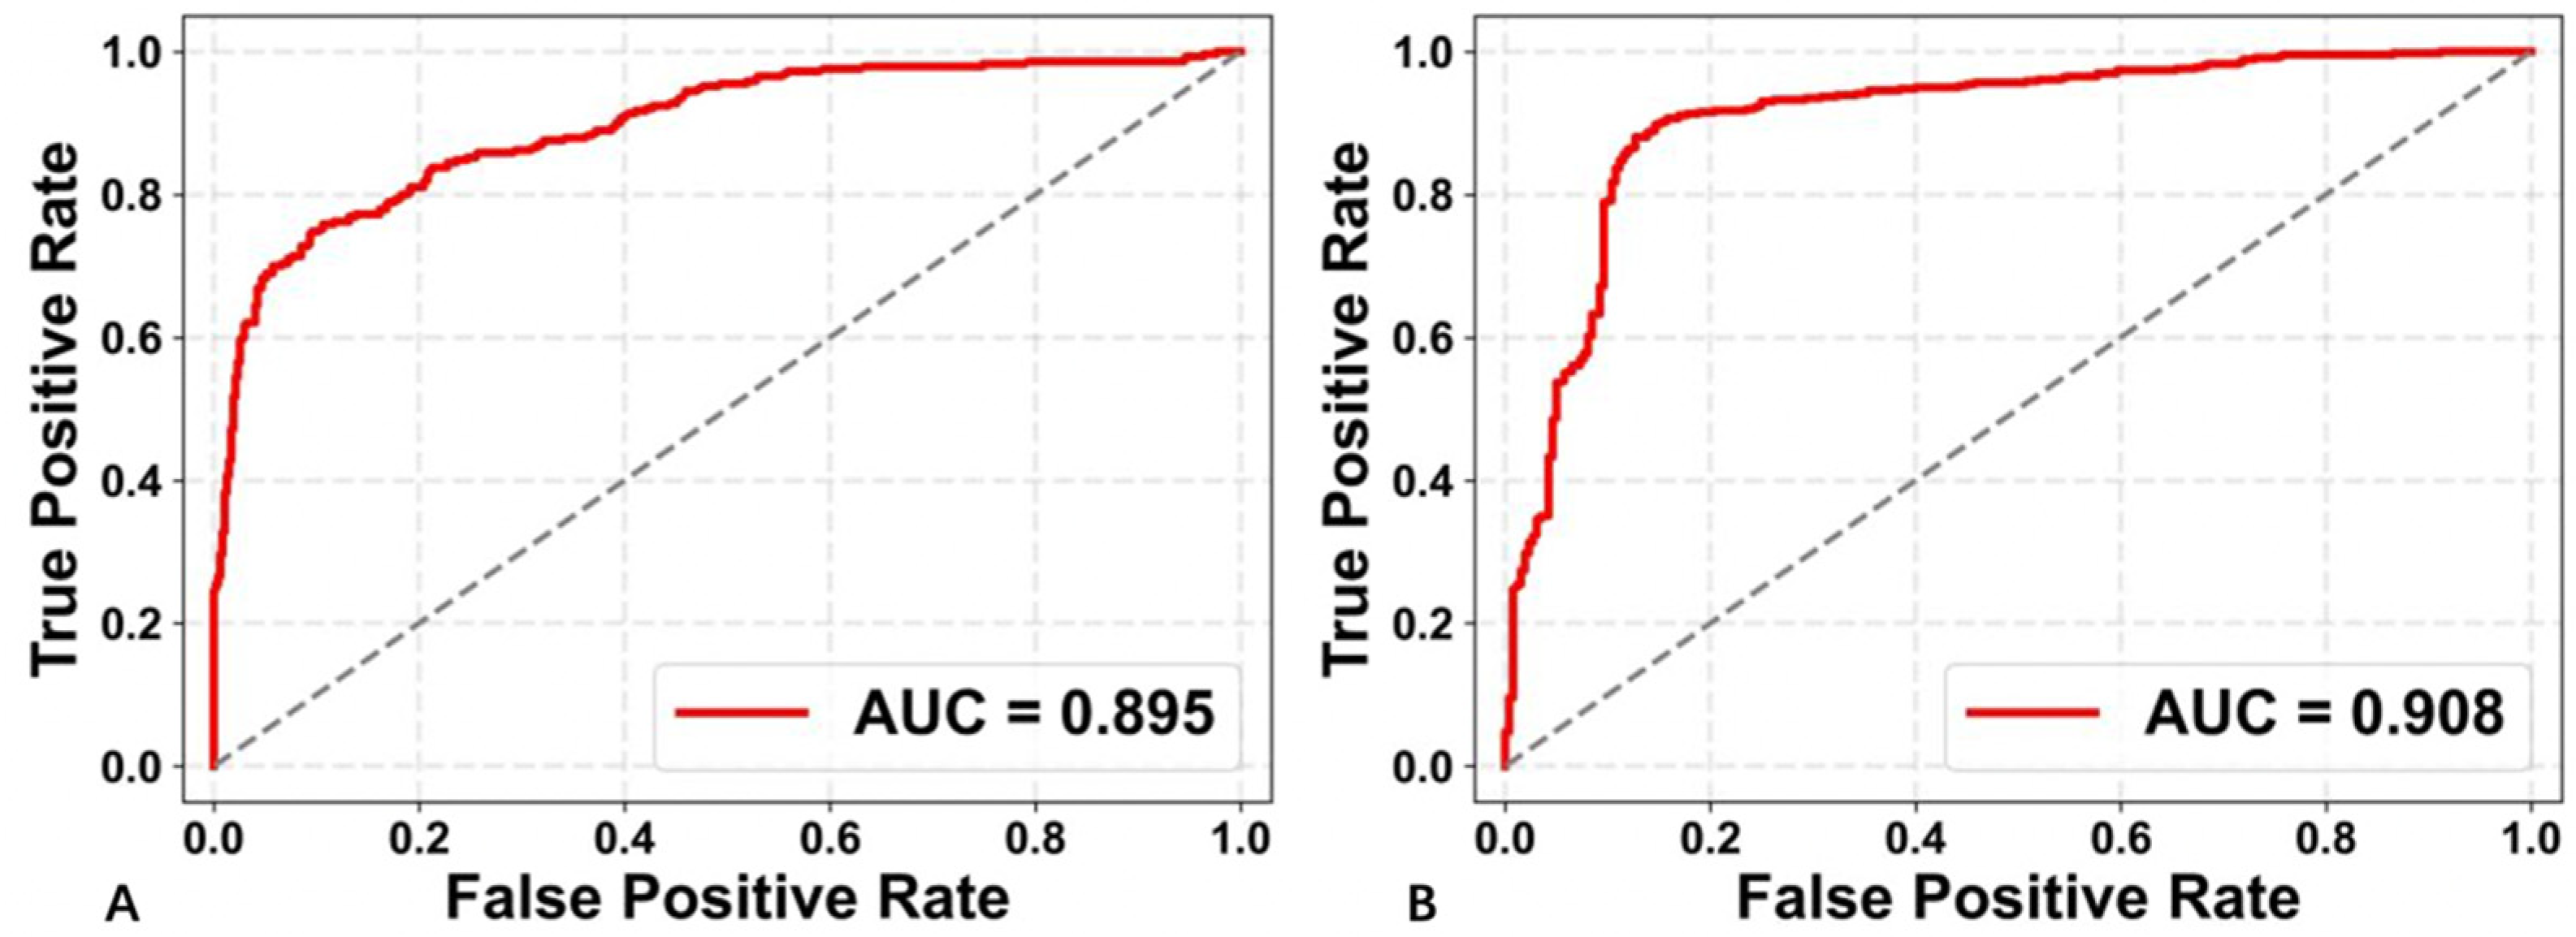

3.2. Performance of the Two Deep Learning Strategies

| AUC | Accuracy | Recall | Precision | F1 Score | |

|---|---|---|---|---|---|

| US+CEUS | 0.895 | 0.829 | 0.759 | 0.786 | 0.772 |

| CEUS-ROI | 0.908 | 0.864 | 0.930 | 0.866 | 0.897 |